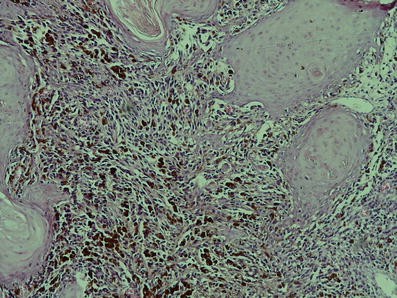

There is junctional activity from epithelium into connective tissue and the epithelium shows pseudoepitheliomatous hyperplasia in histopathologic view

According to the department of maxillofacial pathology, the proposed classification upon histological pattern oral melanoma is divided as melanoma in situ, invasive, and combined [7]; our patient’s lesion was an invasive form. However because of rarity of oral melanoma, data on epidemiology, tumor behavior, treatment, follow-up, and survival of patients are mainly based on single case reports [7, 17].